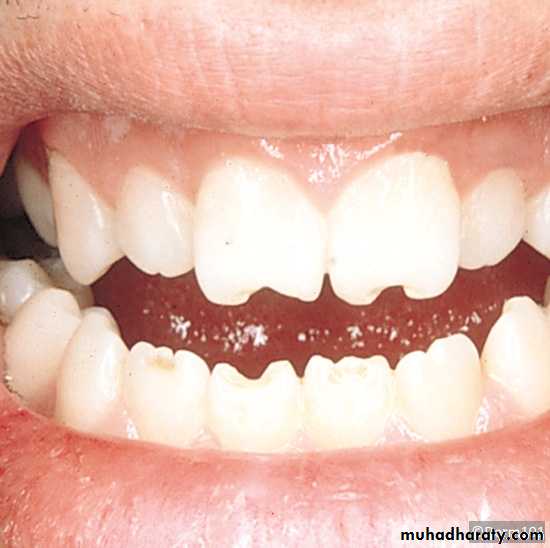

• Thumb and finger sucking: Thumb sucking is defined as the repeated and forceful sucking of thumb with associated strong buccal and lip contractions. It causes• proclination of upper incisors

• retroclination of mandibular incisors

• Increased overjet decreased over bite

• class II occlusion

• Anterior openbite

• Posterior cross bites